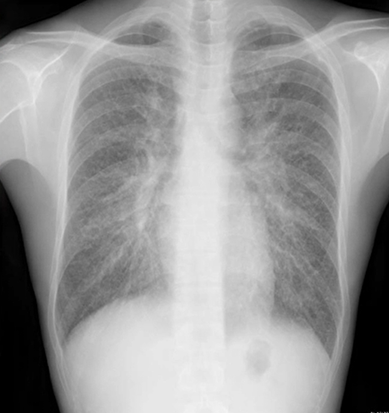

肺紋理(肺の血管や気管支が分岐して網目状に見える模様)がしっかり確認できる胸部レントゲン(X-p)写真

肺紋理がしっかり見えるということは、肺血管の肥大、気管支炎の炎症などが考えられます。合わせてどのような所見があるかも非常に重要になります。

このレントゲン写真では肺紋理がしっかり確認できることに加え肺門部リンパ節が確認できます。このような場合、サルコイドーシス、リンパ腫、リンパ増殖性疾患、癌性リンパ管症を鑑別に挙げます。

CTにて精査に進みます。